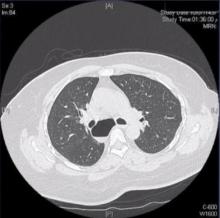

The authors present the case of a complex mediastinal bronchogenic cyst that was excised through a right VATS approach. The anatomy of the mediastinal structures are highlighted, as well as the use of intraoperative endoscopy.